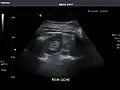

Aorta: Visualized portions normal in caliber, 16 x 15 mm.

Aorta